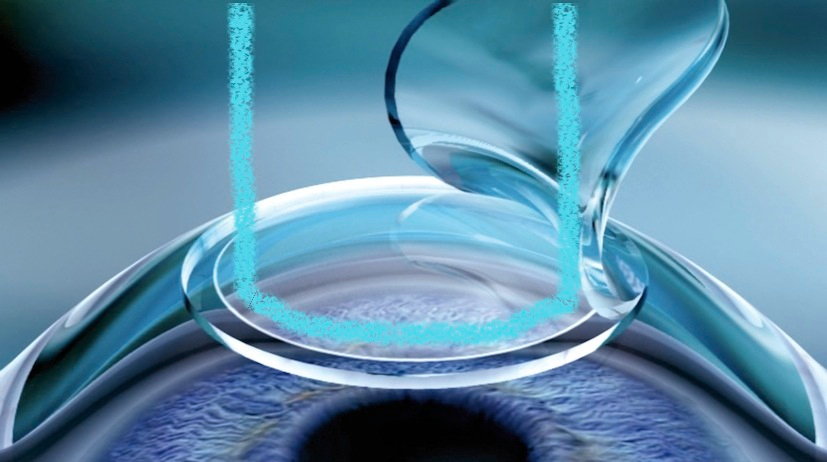

The rest felt like something out of a sci-fi movie, probably because I was on drugs. A rubber ring was placed onto my eye and the doctor said "Vacuum on!". My eyeball felt like it was getting sucked out of my head but there was zero pain. My comfy cushioned platform swung and placed me under another machine. A circle of lights approached the rubber vacuumed to my eye and attached itself leaving total darkness. Stress balls were placed in my hand as I started to feel a bit of anxiety and then I felt pressure as the Femto laser cut around the outside ring through my cornea. This process was repeated for the other eye with no pain once again.

Figure 2: Femto Laser Aftermath